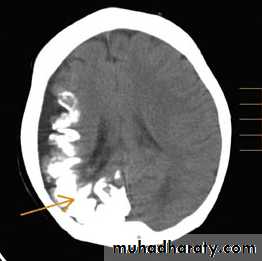

• Sturge-Weber Syndrome

• This syndrome is a sporadic disorder and consists of a constellation of symptoms and signs including a facial nevus (port-wine stain), seizures, hemiparesis, stroke like episodes, intracranial calcifications, and, in many cases, mental retardation.• Clinical manifestations

• 1- Skull x-ray: shows intracranial calcification in the occipitoparietal region in most patients. This characteristically assumes railroad-track appearance.

• 2- Brain CT scan: to detect the extent of the calcification that is usually associated with unilateral cortical atrophy and ipsilateral dilatation of the lateral ventricle.

CT

MRI

• X-Ray

• 3- MRI is a useful to detect the location of the vascular malformation and the presence of white matter lesions.